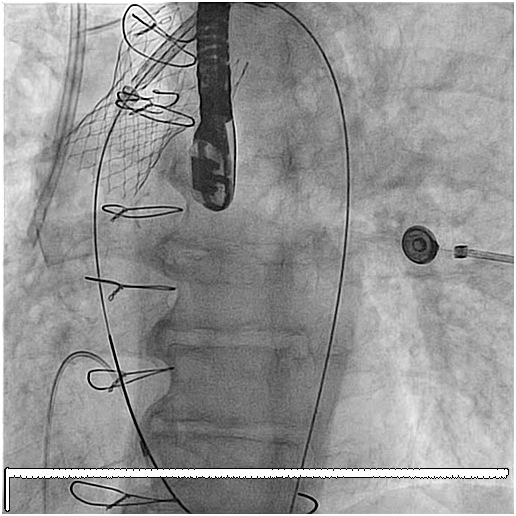

79 y old male patient, known to have diabetes mellitus, end stage renal failure and chronic obstructive pulmonary disease, this patient had aortic valve replacement (AVR) 15years prior, but because of infective endocarditis 7years ago, he underwent a redo AVR (Aortic valve Bioprosthesis) using a 25mm cry preserved aortic homograft implanted as a full root in another hospital. Patient was admitted with severe heart failure and pulmonary edema. His Echocardiogram showed severe AR (Figure 1). Patient was treated aggressively with anti-failure medications. The case discussed in heart team and both options AVR vs TAVI were raised in this high risk patient, with STS score 18. Both the heart team and Family preferred TAVI, According to sizing application this homograft valve will fit with Size 29mm Core Valve, The CT-scan measurements showed an aortic annulus size 21-25mm at different level, Perimeter range from 71-73, 3mm, Aortic valve area 2.9 cm2, and a heavily calcified a tube-like aorta (Figure 2). No clear sinus or junction was seen by CT. A trans-femoral approach for Valve in Valve was used. A 29 mm Medtronic Core valve was deployed and the landmark was the calcium in the root. Unfortunately, it migrated up-ward most probably due to the rigidity of the homograft tube and no real narrowing or calcified leaflet to anchored the valve (Figure 3). Therefore we used another 29 core valve and deployed it through the first one which was well seated in ascending aorta as support. This method of support was very successful for final deployment (Figure 4). It was similar to the melody valve deployment in treating pulmonary regurgitation. There was no aortic regurgitation by Echocardiogram (Figure 5). Patient was very stable and discharged home after 48hours.

Figure 3 The Core Valve migrated up to the ascending aorta immediately after its deployment.